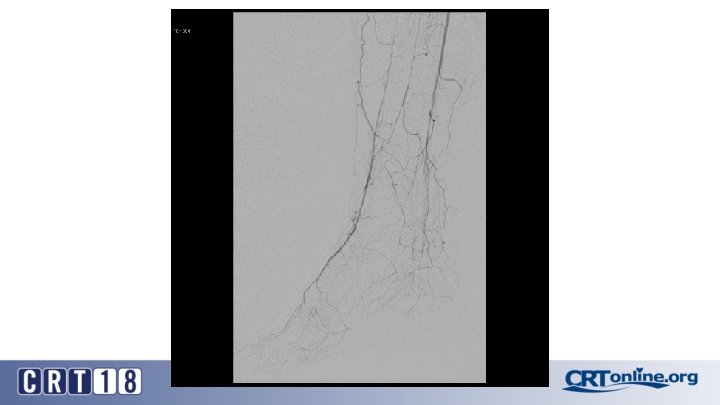

Blue Toe Syndrome

Returns Next day

Failed recanalization: BKA